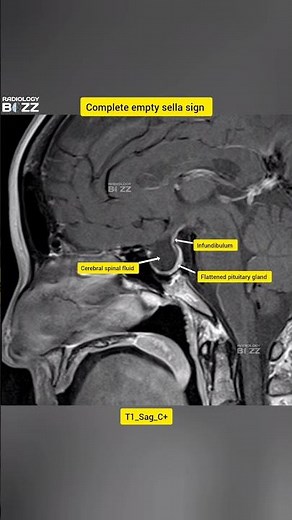

- Partially Empty Sella

Empty Sella - Partially Empty Sella